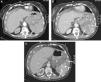

Fractura esplénica. Mujer de 77 años anticoagulada. Caída doméstica como consecuencia de un «mareo». En Urgencias, muestra hipotensión y distensión abdominal. A) TCCC con contraste, cortes axiales del abdomen superior en fase arterial. B y C) Fase venosa. Hemoperitoneo (*).Fuga de contraste e.v. al interior del parénquima esplénico y a la cavidad peritoneal (flecha) que aumenta de tamaño y densidad en la fase portal (b y c) por laceración esplénica con sangrado activo.

Ante sospecha de sangrado activo se realiza un barrido inicial (angio-TC) con el contraste intraarterial, seguido de otro cuando está intravenoso. El rendimiento diagnóstico de la angio-TC es equiparable a la angiografía convencional44, permitiendo detectar sangrado y caracterizarlo como arterial o venoso. La lesión traumática de la pared arterial ocasiona hemorragia activa cuando es completa y, ocasionalmente, la formación de fístula arteriovenosa o pseudoaneurisma, con riesgo de rotura y sangrado tardío, por lo que suelen embolizarse. Por TC aparecen como una dilatación de la luz arterial en la fase arterial que desaparece en la fase venosa, a diferencia de la hemorragia activa, donde persiste la extravasación del contraste (figs. 1 y 4).